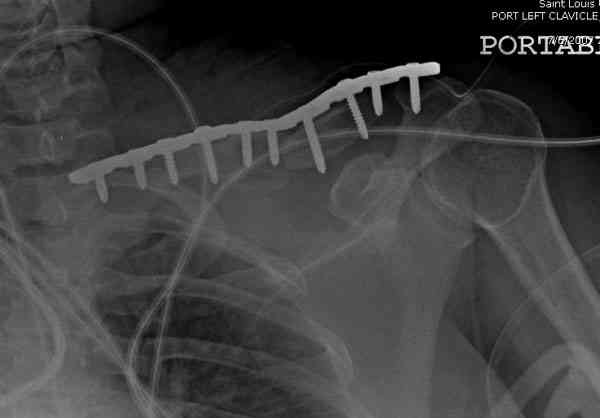

Консервативное лечение, через 8 мес. операция Rockwood pin с костной пластикой в нашем городе другим врачом. После 8 недели падение, гвоздь удален оперирующим хирургом, больная направлена к нам. Фиксация реконструктивной пластиной с трикортикальным графтом, добавлен BMP-2. Для стабилизации фиксацию провели через акромион.

Вот уже два месяца больная также продолжает жаловаться на боли, буквально на днях удалили акромиальную часть пластины с специальной пилой с алмазным покрытием для медицинского металла. До сих пор судьба ложного сустава неизвестна....